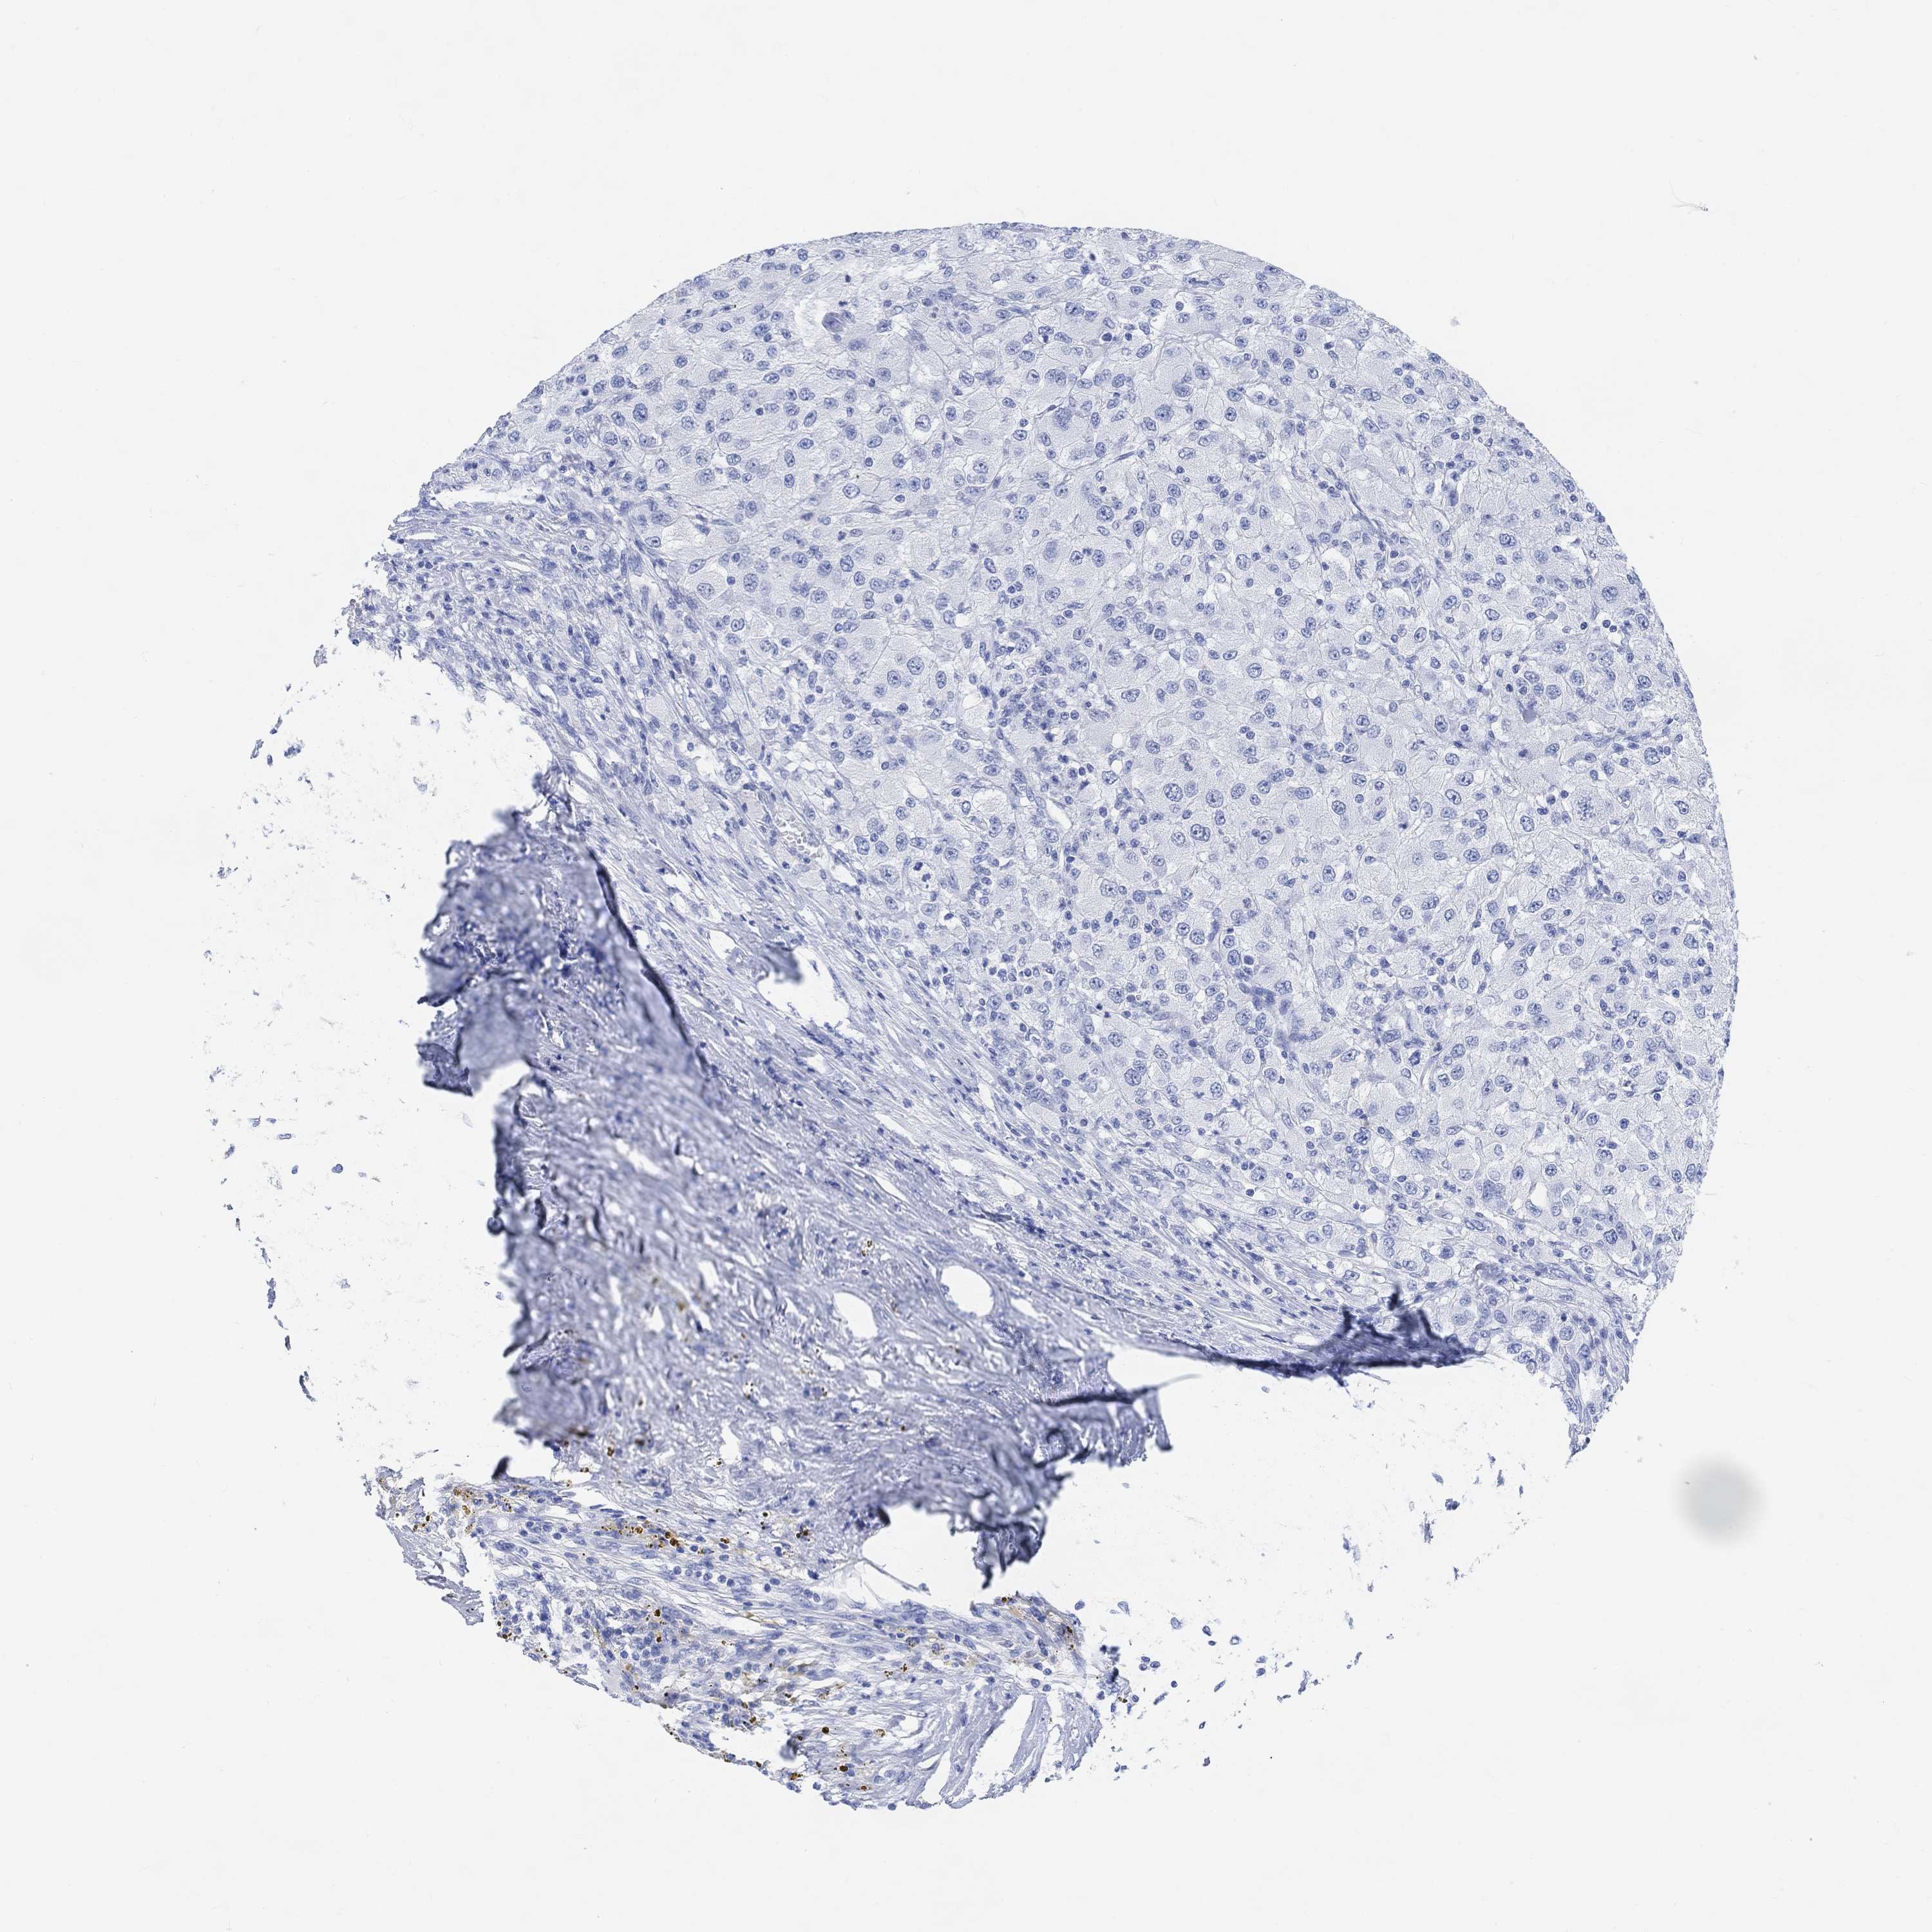

CANCER RENAL CANCER Show tissue menu

KICH TCGA KIRC TCGA KIRC VALIDATION KIRP TCGA PROTEIN RCC CPTAC PROTEIN EXPRESSION